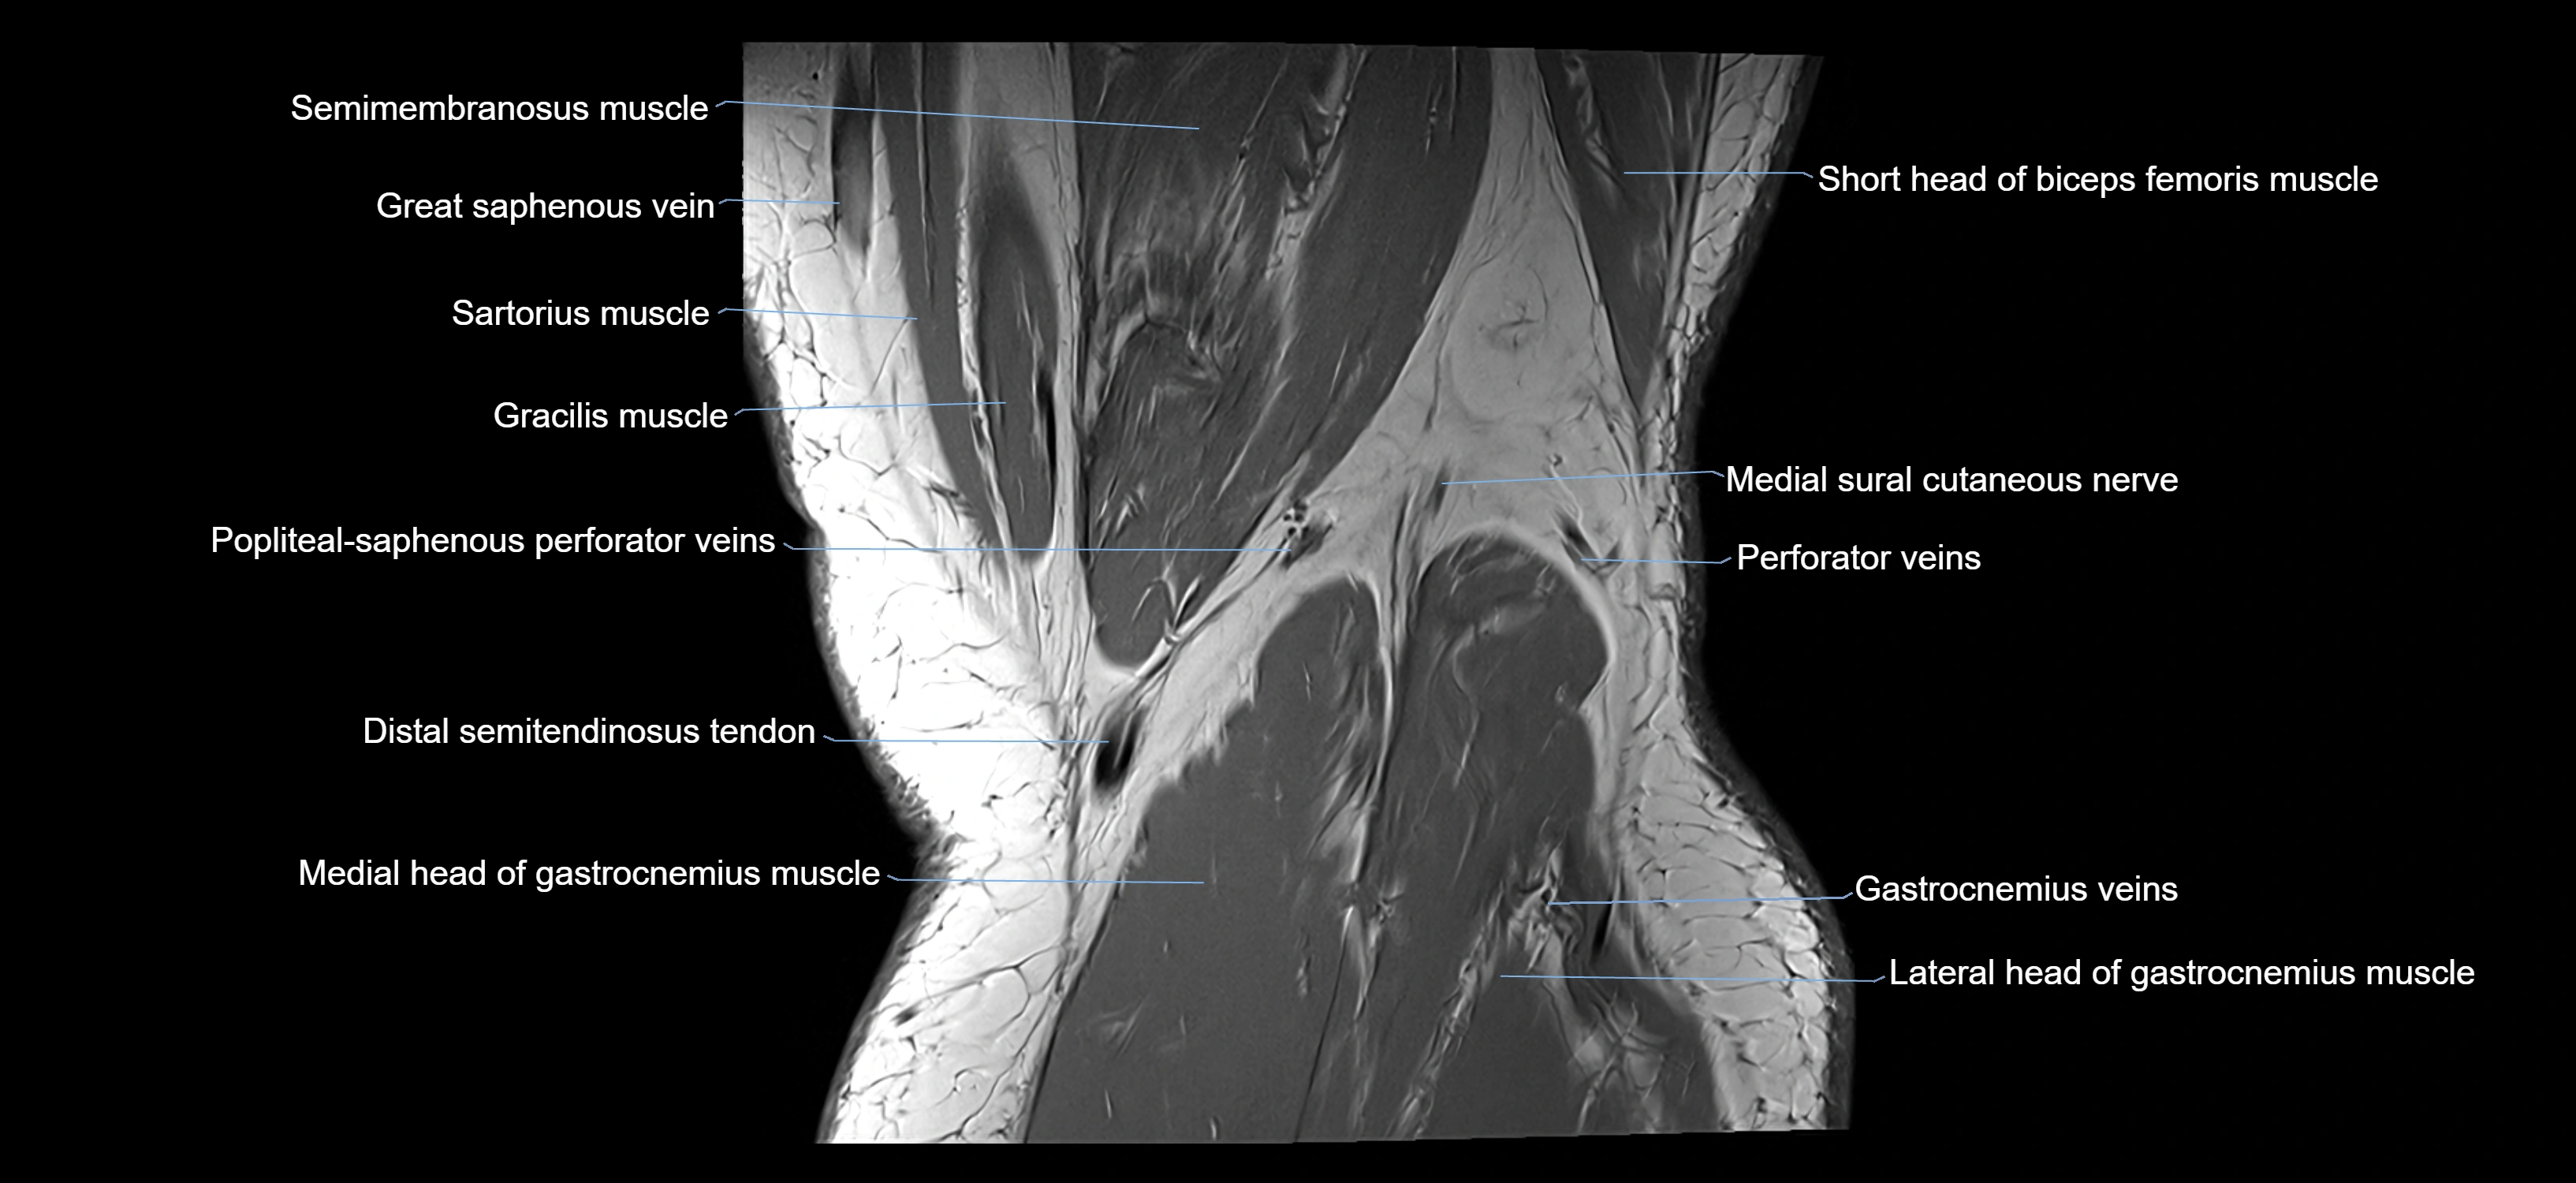

- Semimembranosus muscle

- Semitendinosus muscle

- Sartorius muscle

- Gracilis Tendon (Proximal)

- Distal semitendinosus tendon

- Medial head of gastrocnemius muscle

- Lateral head of gastrocnemius muscle

- Medial sural cutaneous nerve

- Popliteal–Saphenous perforating veins

- great saphenous vein

- Biceps femoris muscle (Short head)